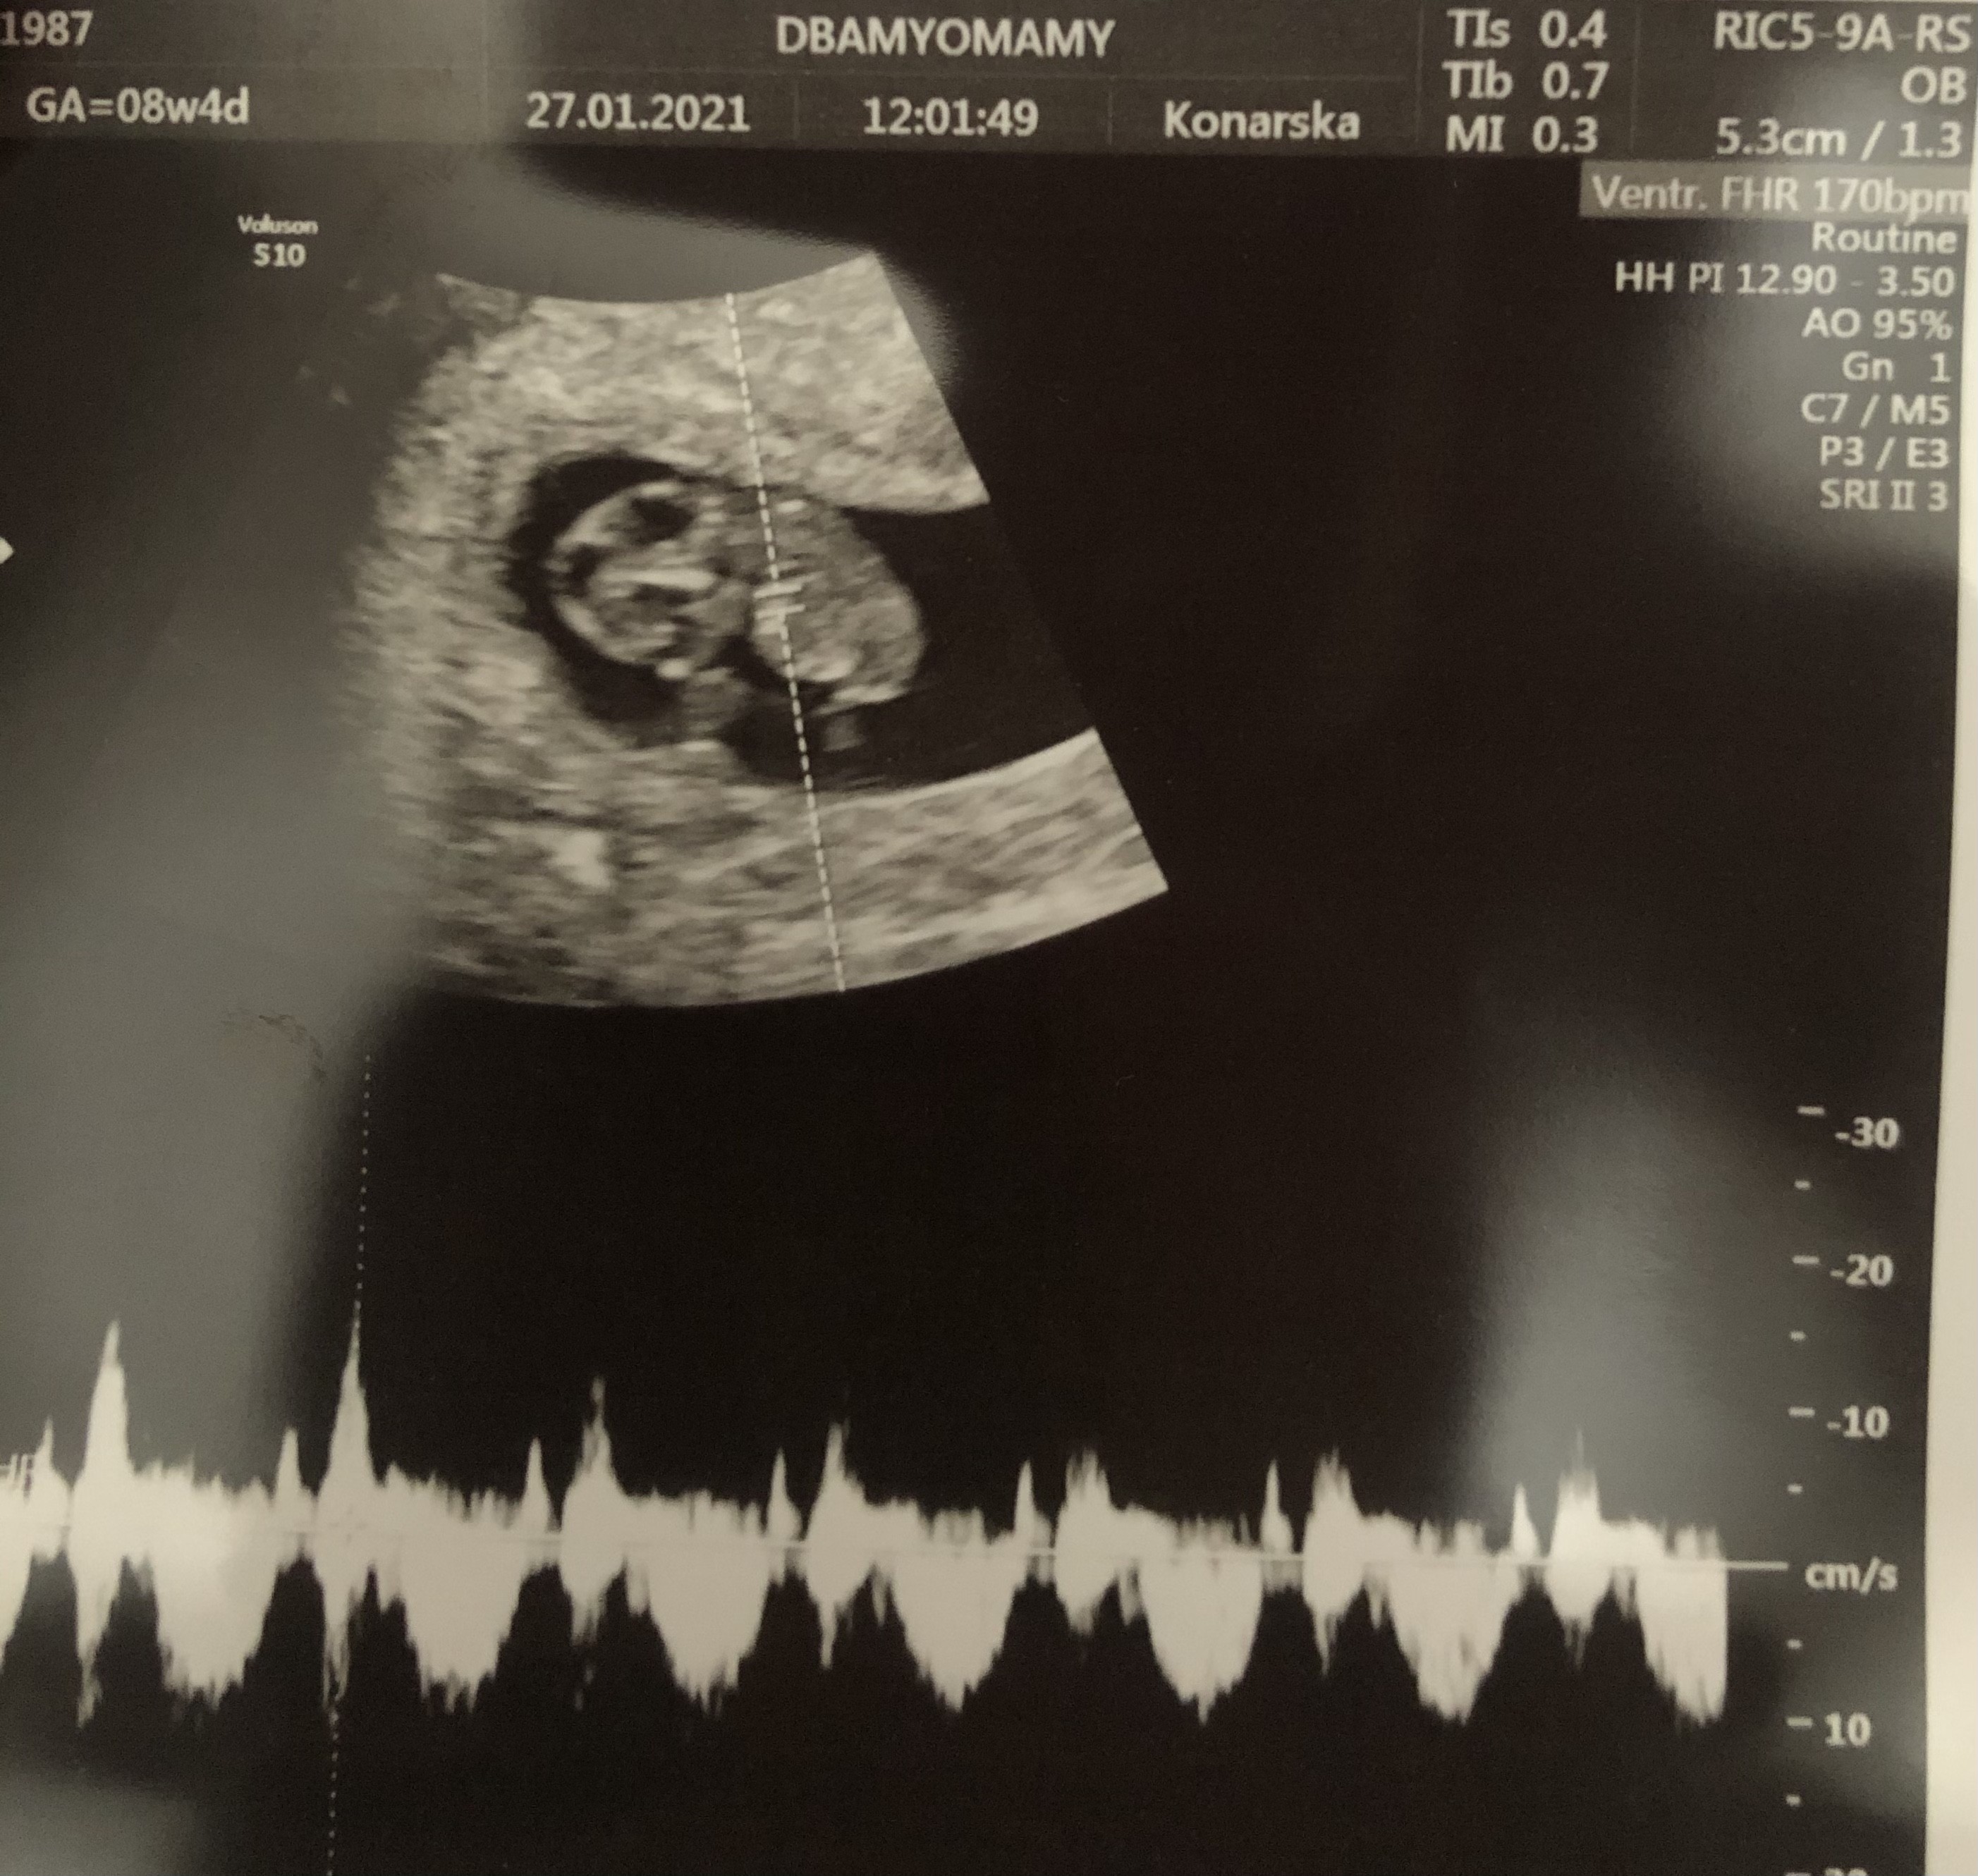

Cześć :) ja już po wizycie :) wszystko super :) Dzidza ma 19 mm i 170u/min. Mega wzruszające uczucie usłyszeć serduszko, łezka poleciała ☺️☺️

• 3E8BE742-8CD2-4EED-9022-4DC0E2E65458.jpeg

3E8BE742-8CD2-4EED-9022-4DC0E2E65458.jpeg

1,1 MB · Wyświetleń: 127